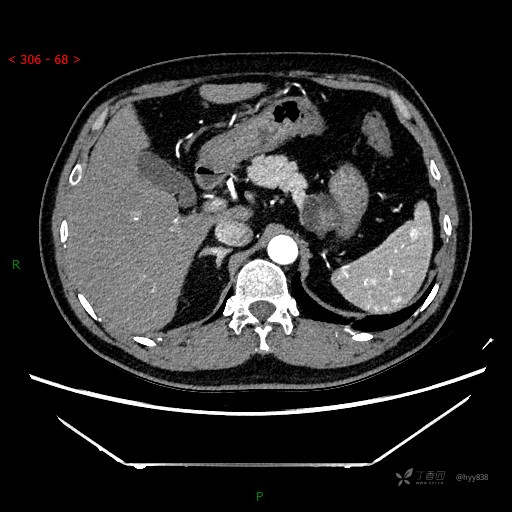

增强动脉期